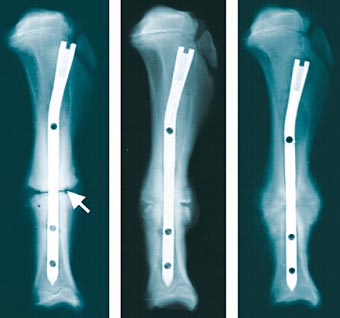

Knochenbruche Behandlung Operativ Und Konservativ